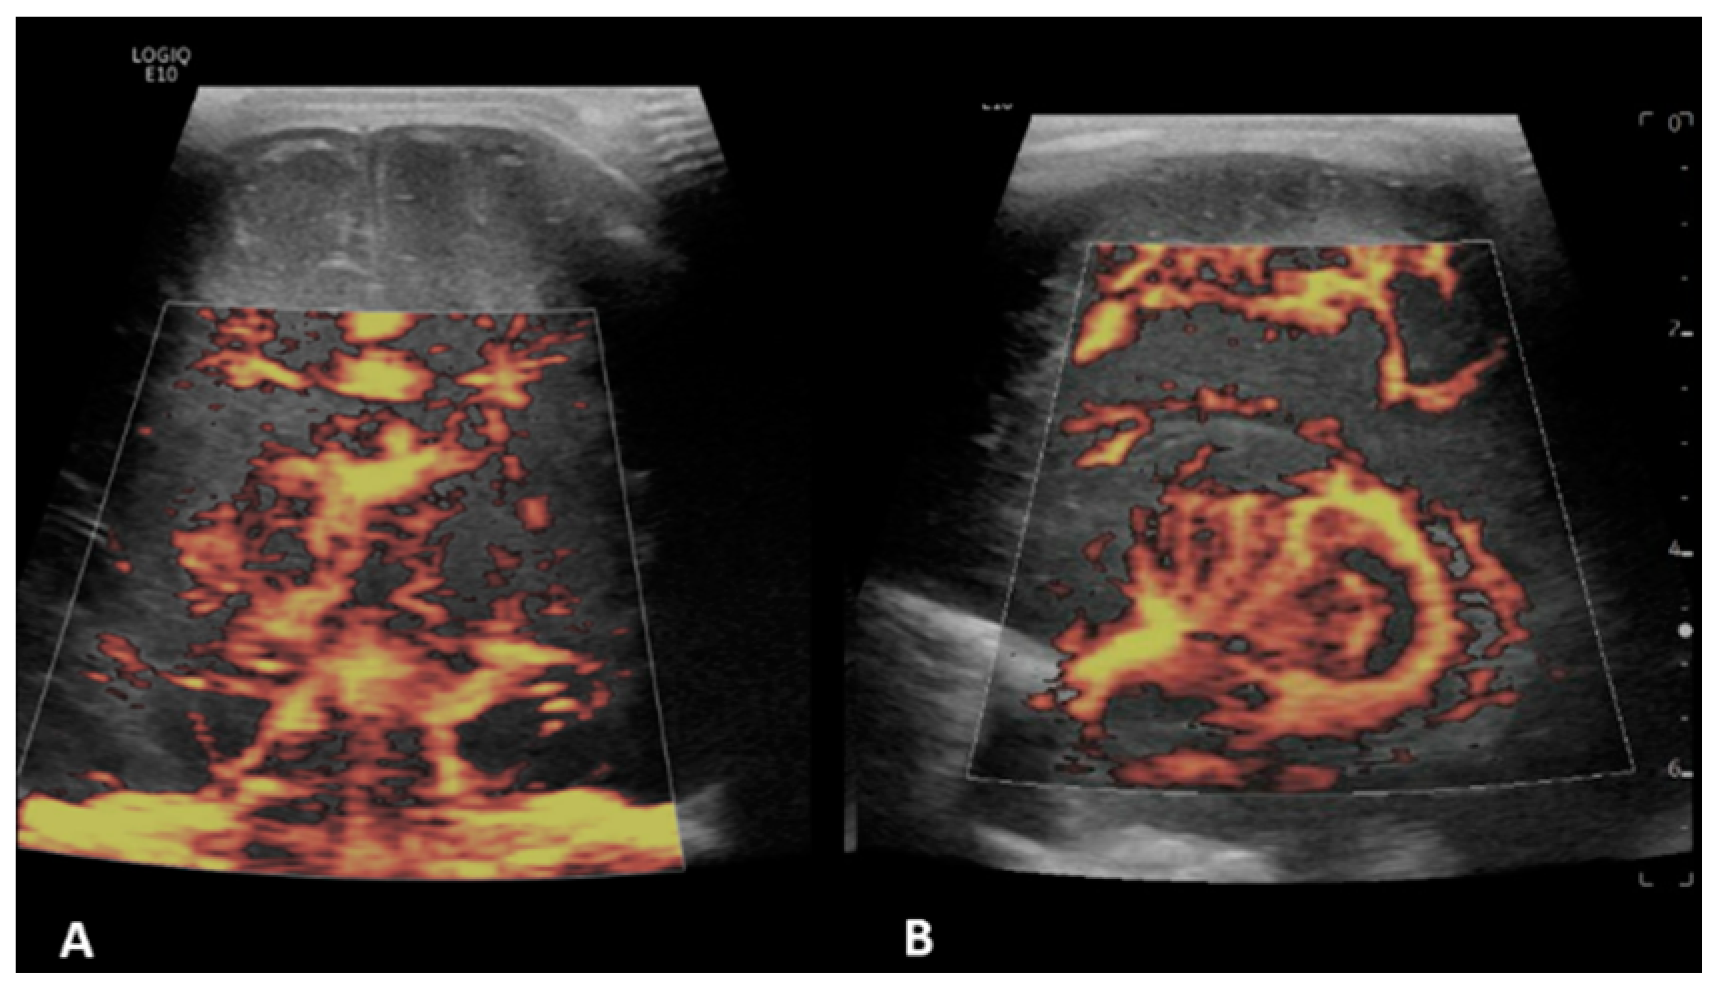

- Hwang, M.; Haddad, S.; Tierradentro-Garcia, L.O.; Alves, C.A.; Taylor, G.A.; Darge, K. Current understanding and future potential applications of cerebral microvascular imaging in infants. Br. J. Radiol. 2022, 95, 20211051. [Google Scholar] [CrossRef] [PubMed]

- Barletta, A.; Balbi, M.; Surace, A.; Caroli, A.; Radaelli, S.; Musto, F.; Saruggia, M.; Mangili, G.; Gerevini, S.; Sironi, S. Cerebral superb microvascular imaging in preterm neonates: In vivo evaluation of thalamic, striatal, and extrastriatal angioarchitecture. Neuroradiology 2021, 63, 1103–1112. [Google Scholar] [CrossRef]

| Peri-gyral flow (n = 10) | 7/12 (58.3%) | 0.09 | 8/14 (57.1%) | 0.07 | 2/2 * (100%) | 0.08 | 3/6 (50%) | 0.63 | 3/5 (60%) | 0.35 | 2/3 (66.6%) | 0.35 |